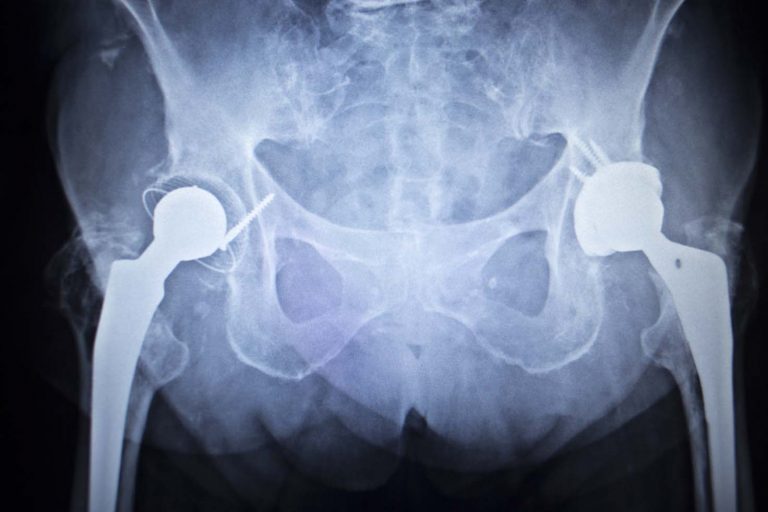

It is estimated that over 500,000 people received metal-on-metal hip implants over the last 10 years in the U.S. alone. The dangers associated with these devices—which fail at an alarming rate—are well documented.

The metal-on-metal movement inside the human body can cause the release of tiny metal particles. This can damage the surrounding soft tissue and bone. It may even enter the bloodstream causing other systemic health issues. Failure often requires revision surgery to remove or replace the implant.

The sky-high failure rates of metal-on-metal hip implants are evidenced by the number of revision surgeries and thousands of lawsuits brought by injured plaintiffs. There are two types of metal-on-metal hip implants:

Traditional total hip replacement systems

Resurfacing hip systems

According to an investigative report in the esteemed British Medical Journal, average failure rates at seven years were 11.8% for resurfacing hip systems and 13.6% for total hip replacement systems (with some variance among brands), as compared to rates of 3.3%-4.9% for hip implants made from other materials. The FDA received more than 12,000 complaints in 2011 alone relating to these devices.